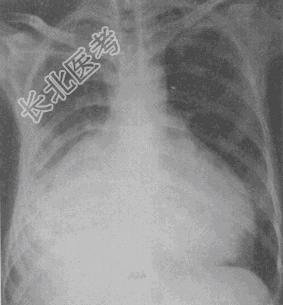

- 单项选择题患者,女, 26岁,端坐呼吸、乏力、腹胀, 心音遥远,胸部正侧位摄片示心影增大, 如图,最可能的诊断是

A、心包积液

B、缩窄性心包炎

C、扩张性心肌病

D、肥厚性心肌病

E、风湿性心脏病二尖瓣狭窄